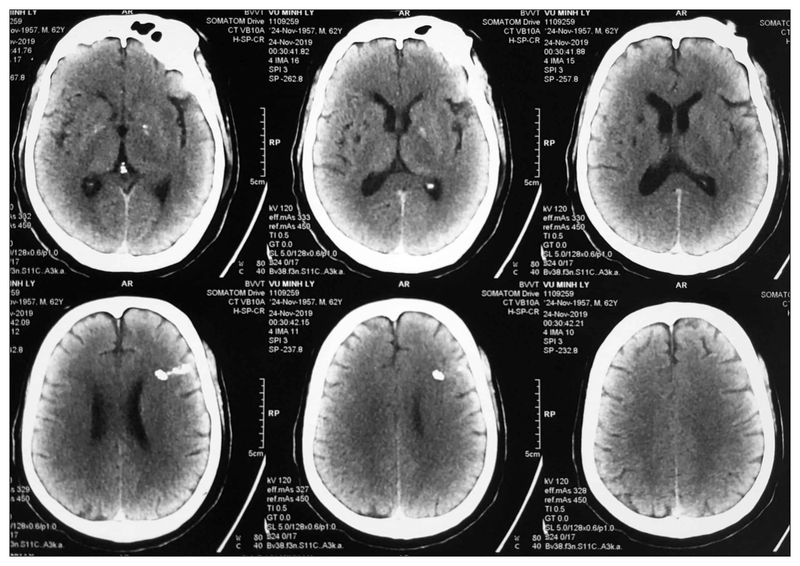

Tại đây, các bác sĩ sẽ tiến hành một loạt các xét nghiệm cận lâm sàng như: Chụp CT Scanner, chụp MRI, chụp động mạch đồ,... để đánh giá tình trạng và đưa ra kết luận chính xác về tụ máu não, từ đó xác định phương pháp điều trị phù hợp nhất cho người bệnh.